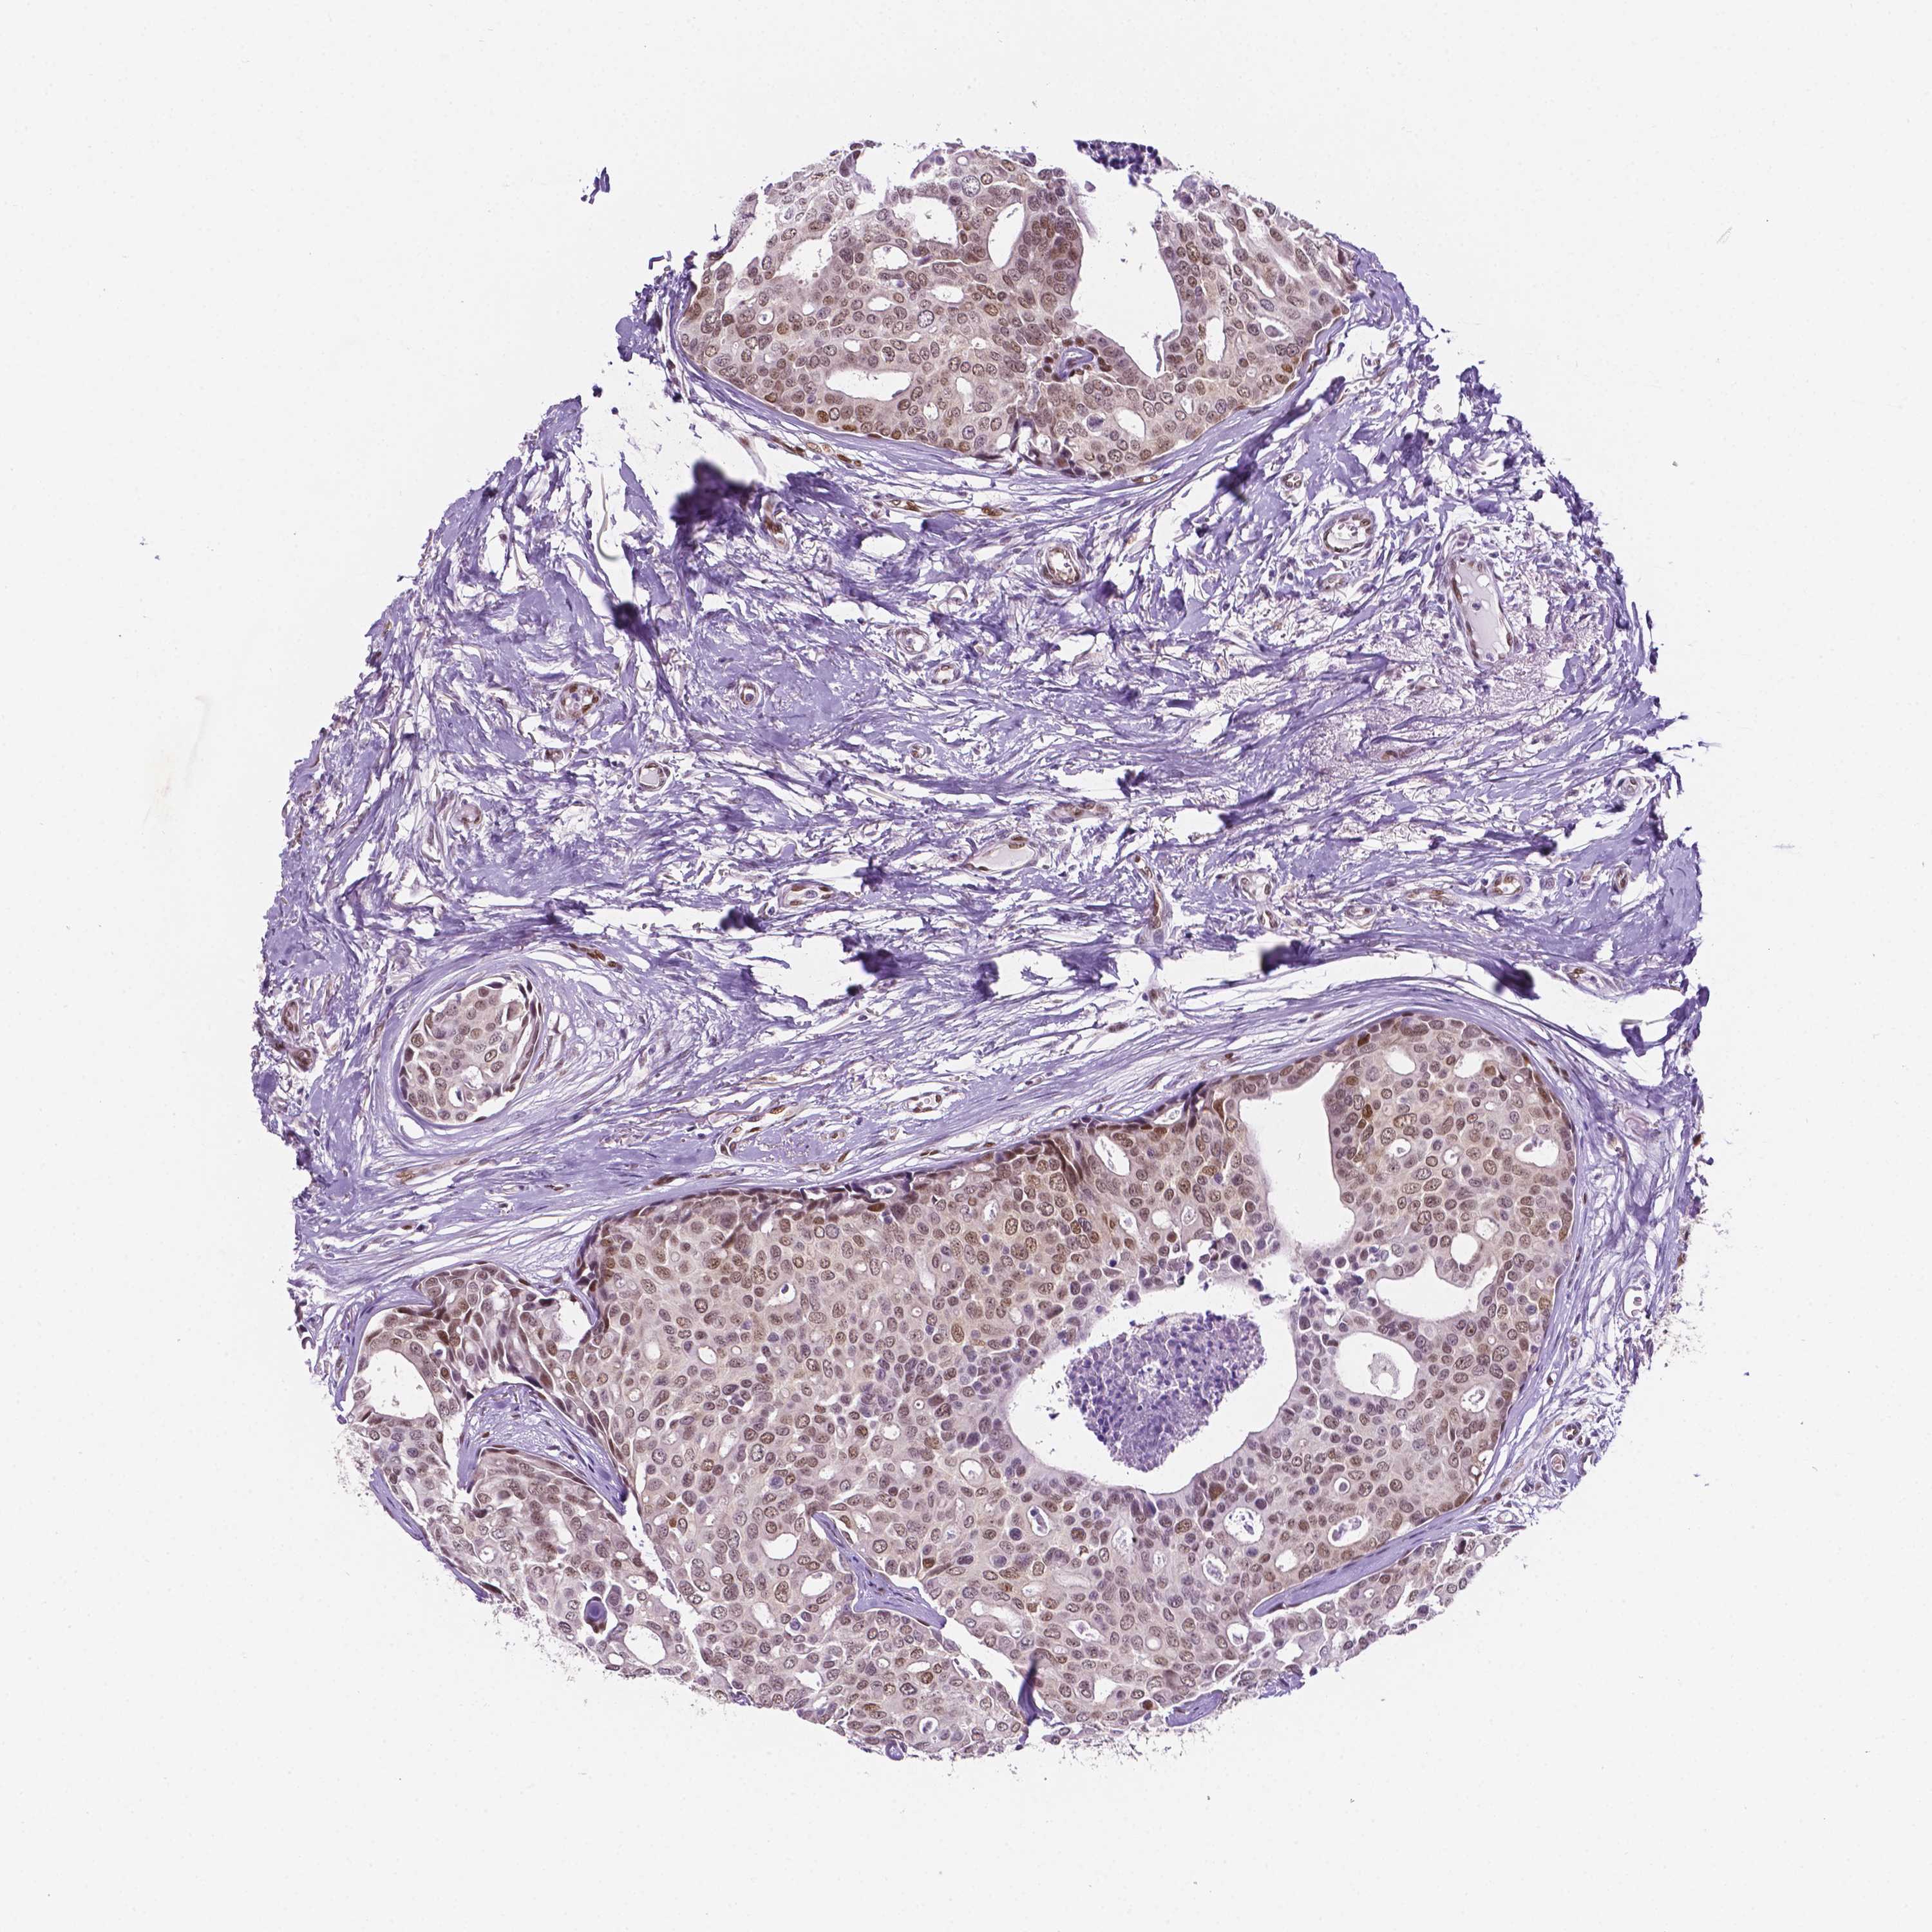

CANCER BREAST CANCER Show tissue menu

BRCA TCGA BRCA VALIDATION PROTEIN EXPRESSION

Breast cancer

Human cancer